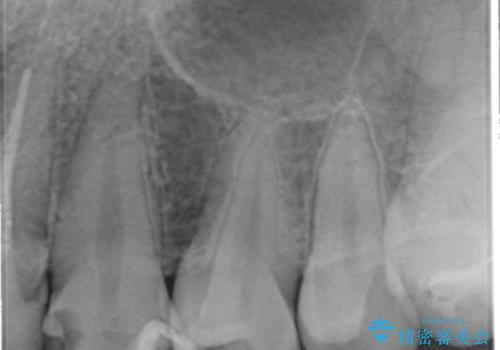

精査したところ、ほとんどの歯が保険内のレジンで充填されており、咬み合わせも悪く咬合していない歯もありました。

虫歯をしっかりと治療したのち、オールセラミッククラウンによる補綴治療を行いました。

下顎の埋伏していた親知らずも抜去しました。